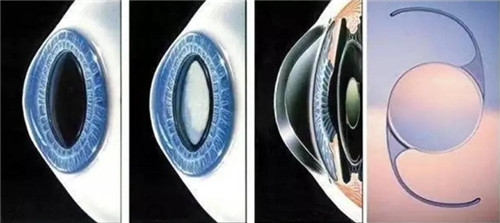

白内障手术是一种非常常见且安心的眼科手术,通常采用超声乳化技术将模糊的晶状体取出,然后植入人工晶状体以改善眼部视力。